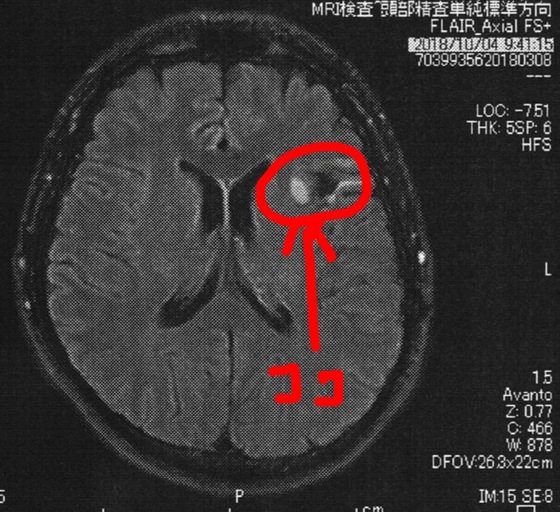

今回2018/10/4(手術後51か月)のMRI画像

MRI検査の結果、半年前と比べても変化は無いように見えるが、

一年前やそれ以前の画像と比べると若干変化があるようにも見える。

と先生が言う。

半年毎の検査ではMRI画像上は変化が無いように見えてたけど、年単位の時間ではちょっとづつ増えているんだろうなぁ。。。